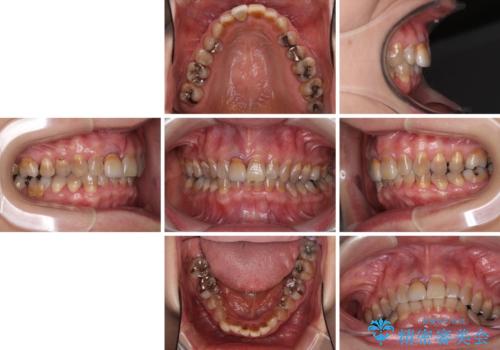

- 前歯のデコボコと、顎に負担のかかる歯並びを改善したいとのことで来院された患者様です。

うまく歯ぎしりができず、強く食いしばりをしてしまう咬み合わせであったため、奥歯に非常に負担がかかっていました。

インビザラインを用いて前歯のデコボコを改善するとともに、奥歯の咬み合わせを変えてスムーズに歯ぎしりできるように排列していくこととしました。

可能であれば上下正中を合わせ、左右の咬み合わせも改善したかったのですが、骨格的な左右差が大きかった上に、インビザラインでは限界があり、達成できませんでした。

それでも奥歯の負担を改善することができました。